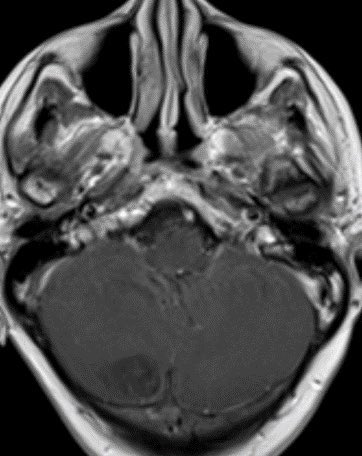

🔷Imaging:

💡 Most medulloblastomas enhance except group 4 which may have minimal to no enhancement

💡 Most important job as a rad is to search for metastatic disease (leptomeningeal and systemic)!

💡 Both Lhermitte-Duclos & Medulloblastoma SHH can have a striated appearance! Use DWI/ADC, density on CT, & enhancement to distinguish!